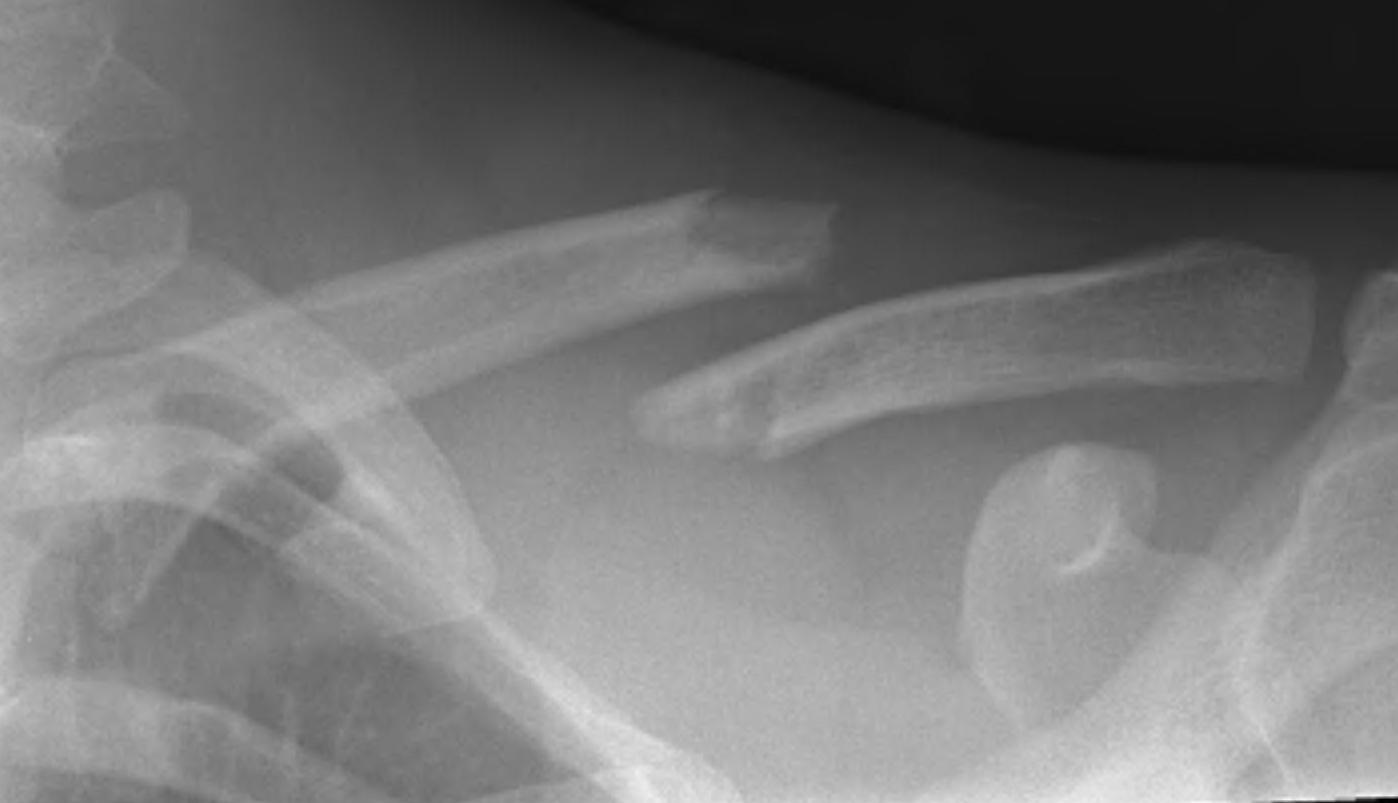

Z shaped midshaft clavicle fracture

Shortening

Displacement

- the proximal fragment elevated by sternocleidomastoid

- lateral fragment sags down with weight of shoulder